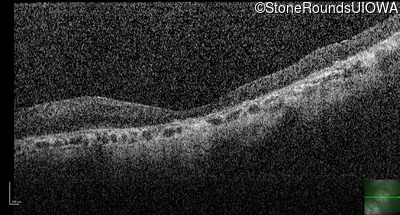

OD

OS

1/200 sc

Age at visit:

76 years

OCT Stack